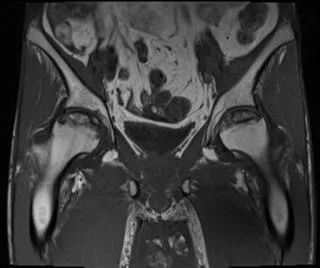

双侧股骨头前上面有大面积的骨髓异常,T1为低信号,在T1和T2W图像上,周围环绕着低强度的边缘。双股骨头呈线性软骨下骨折/断裂,在脂肪抑制图像上得到很好的评价。两侧均有轻度塌陷/扁平的轻微轮廓畸形。这些发现代表了双侧股骨头缺血性坏死。

骶髂关节和耻骨联合正常。

盆腔内存在小体积游离液。弥漫性软组织水肿见于前腹壁及骨盆、大腿。这些发现是由于慢性肾脏疾病造成的。